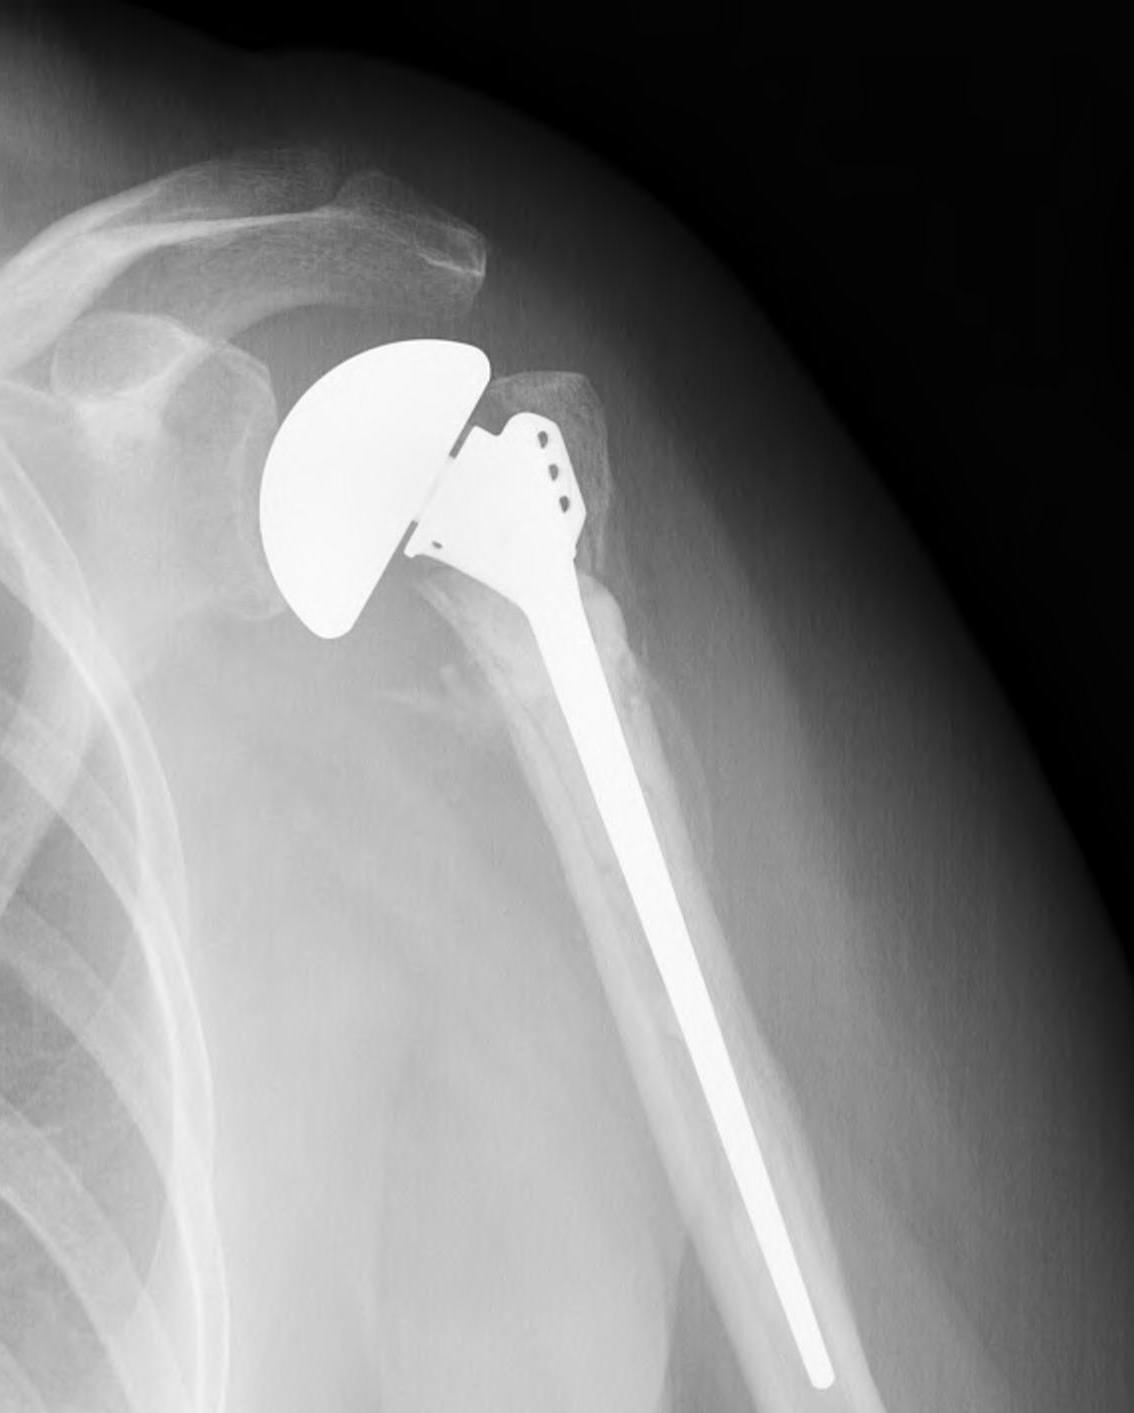

proximal humerus fracture Background ORIF with locking plate Arthroplasty Greater tuberosity fractures Lesser tuberosity fractures / avulsions Book traversal links for Proximal humerus fractures ‹ Pectoralis Major Tears Up Background ›